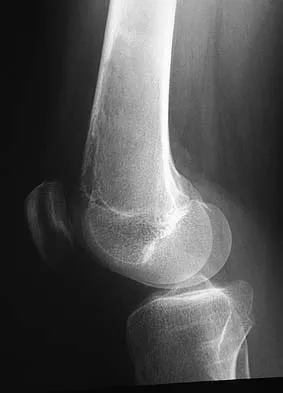

A 15-year-old boy reports leg pain after being tackled during football practice. Radiographs and a CT scan are shown in Figures 46a through 46c. The patient has a pathologic fracture through what underlying lesion?

The images show a lobulated, eccentric, well-marginated lesion that is typical of a nonossifying fibroma. The lesion is slightly expansile, and the CT scan findings show that the lesion is very well marginated and the cortex is disrupted, which is a common finding. None of the characteristics of this lesion is aggressive in nature. Menendez LR (ed): Orthopaedic Knowledge Update: Musculoskeletal Tumors. Rosemont, IL, American Academy of Orthopaedic Surgeons, 2002, pp 69-75.